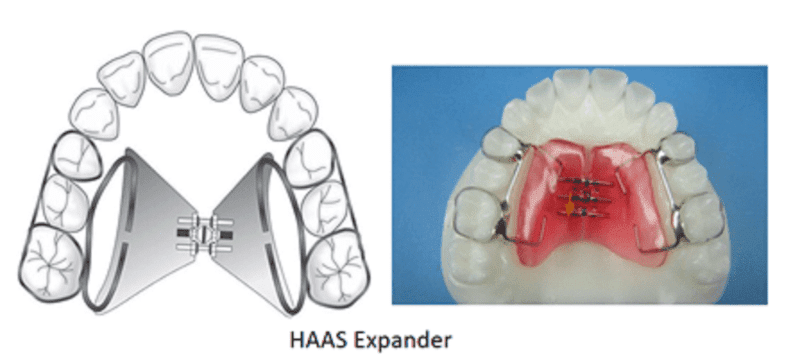

Tooth and tissue-borne appliances: Derichsweiler or the Hass type of appliances

Haas type: This appliance is a rigid appliance which not only transmits forces on to the teeth but also on to the palatal shelves directly. Heavy stainless steel wire (0.045 inch/1.15 mm) is welded and soldered along the palatal aspects of the band. The free ends are turned back to be embedded in acrylic plate which contains an expansion screw in the midline. Both Derichsweiller and Haas types use similar kinds of screws.

In Haas and Hyrax, the screw is activated once or twice a day, normally 0.2 mm per activation, and both appliances have been shown to be effective in correcting transverse maxillary deficiency (Weissheimer et al., 2011). Every turn of the screw opens the appliance by 0.25 mm. Each turn involves 90° activation.